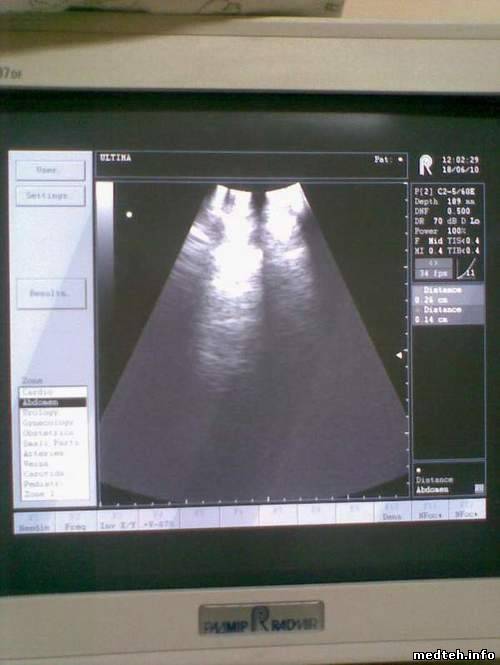

Аппарат УЗИ Ultima pro фирмы "Радмир", Украина, в развертке темная полоса.

Подозрение на датчик. Что можно с ним сделать?

Боюсь, сами ничего сделать не сможете. А с учетом того, что есть еще одна узкая темная полоска слева, в датчике идут необратимые процессы и долго он не протянет.